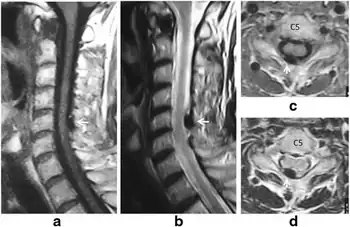

- Spinal disc herniation – protruding or bulging discs, or if severe prolapse.

- Spondylosis - degenerative arthritis and osteophytes

- Spinal stenosis – a narrowing of the spinal canal